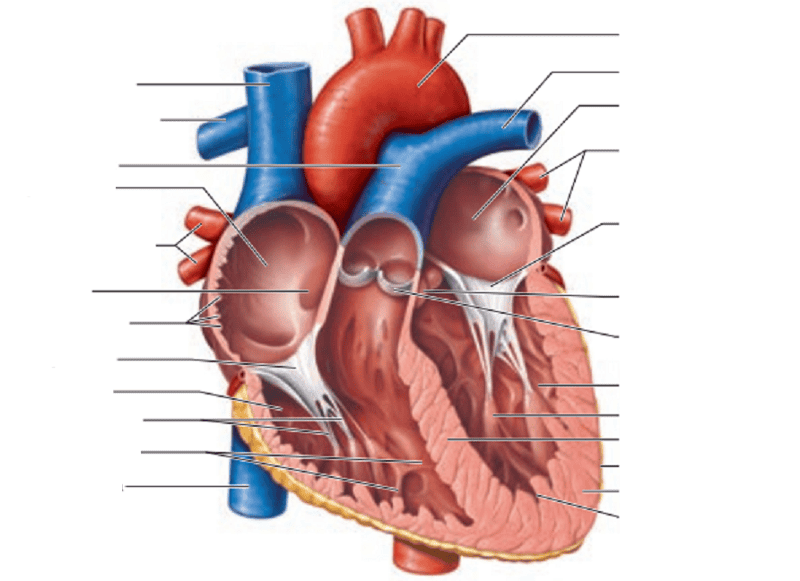

Name the missing parts.

External posterior view

Name the missing parts.

External posterior view

Name the missing parts.

External posterior view

Name the missing parts.

External anterior view

Name the missing parts.

Frontal section